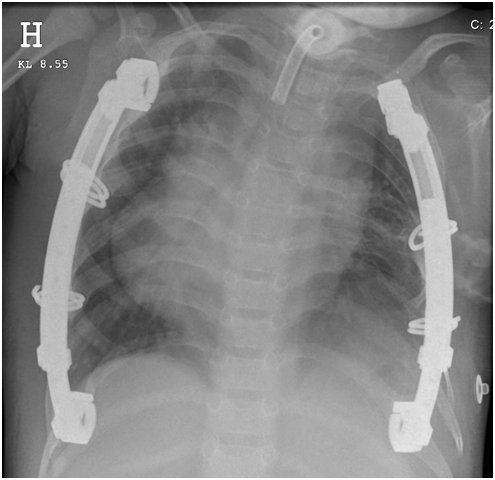

Due to the lack of other options and the patient’s rapid deterioration and life-threatening TIS, we agreed with the parents and the patient should undergo a sternal distraction procedure. To avoid problems with skin closure, the plastic surgeons applied a skin expander on the anterior parts of the left hemi-thorax several weeks before the procedure. In October 2011, an osteotomy of the sternum from the incisura jugularis to the processus xiphoideus was performed, and a 3-centimeter distraction of the sternum was achieved. The sternum was fixated with plates and screws (MXTGsternalFix5743F. DePuySynthes, Switzerland) (Figure 3). A structural autologous graft was used to fill the sternum diastasis (Figure 4).

After surgery, the patient experienced significant clinical improvement. His respiratory values stabilized, and his pulmonary artery values decreased to within the normal range. In November 2013, a second distraction of the sternum and an acute distraction were performed with the intention of further increasing the thoracic cage volume, both to optimize the patient’s respiratory function and to accommodate his growth. During surgery, the fully integrated bone graft at the bone transplantation site was noted. The patient’s sternum was again distracted 3 centimeters and was fixated with plates and screws (MXTGsternalFix5743F. DePuySynthes, Switzerland). The procedure was identical to the procedure performed in 2011, and the surgery and post-operative care were uneventful.